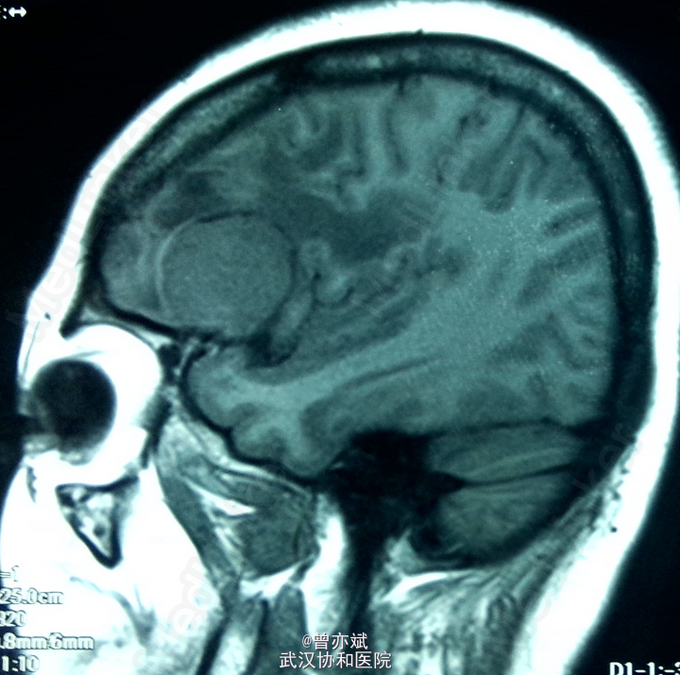

蝶骨嵴 or 大脑凸面脑膜瘤?

患者女,48岁,因“头晕1年”入院。近来出现左侧肢体肌力下降。

查体除左侧肢体肌力稍差4+,余无阳性体征。MRI如下